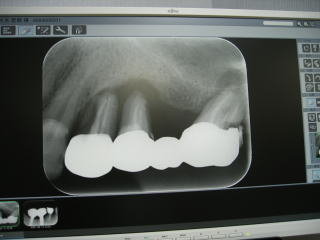

令和3年8月、平成元年の開業以来、約33年間お世話になったアナログレントゲン2台に別れを告げ、

最新式のデジタルレントゲン2台(全体のパノラマ、一部分のデンタル)を導入しました。

患者さん説明用のiPadを診療台サイドまで持って行き、見てもらい説明しています(写真2枚目の中央がiPadです)。

患者さんの被ばく量は従来の1/5〜1/10以下となり、より安全性が増しました。

なおかつ、短時間で鮮明な画像が得られ、診断や治療に大いに役立ち、患者さんにも好評です。